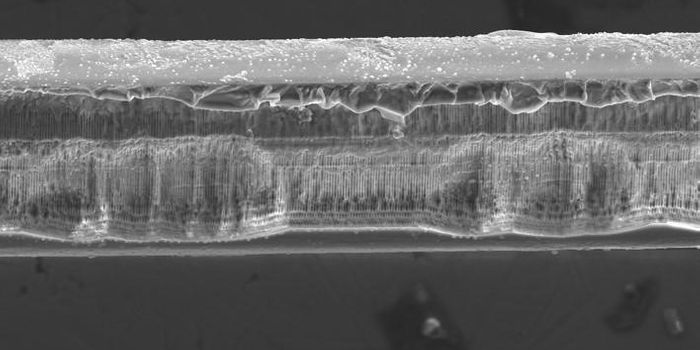

AUG 01, 2016Clinical & Molecular DXMuch like the bacteria that build plaque in your teeth, bacteria can colonize medical implants as slimy films that cause ...